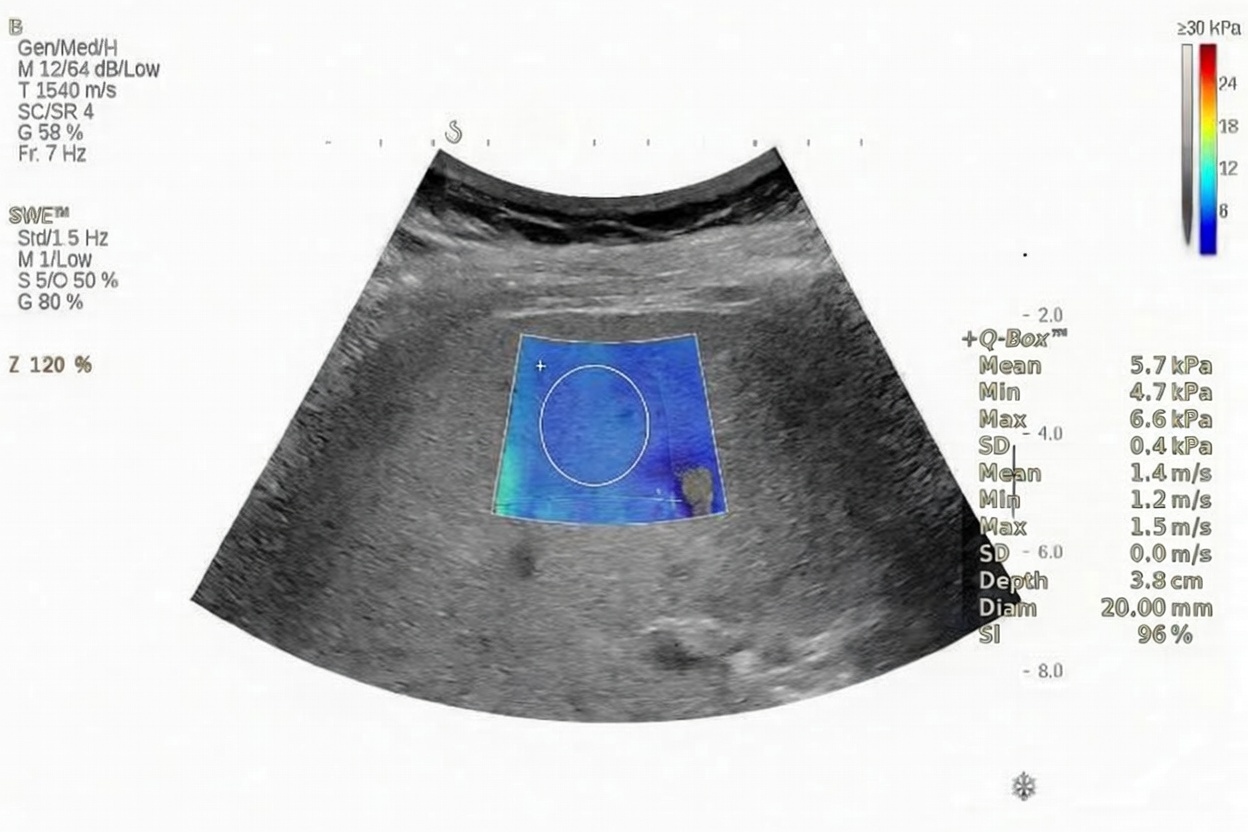

Shear Wave Elastography

Shear Wave Elastography is an ultrasound-based technique that measures liver tissue elasticity in real time.

Key advantages:

Excellent spatial resolution

Ability to assess both focal and diffuse liver disease

Ideal for longitudinal follow-up

Can be performed along with routine ultrasound examination

It is particularly useful for monitoring treatment response and disease progression over time.